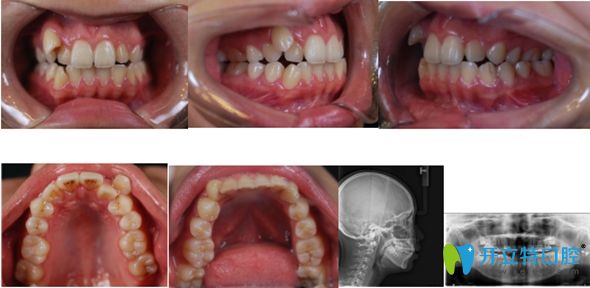

網(wǎng)紅小哥哥在佳美口腔矯正前的牙齒照

<讓小哥哥一直很傷腦筋的亂牙圖>   ↑ ↑

于是乎,終于在粉絲們的千呼萬喚下,開始了他的整牙之旅。采用的是小巧而精致的金屬自鎖托槽矯正。小哥哥在復(fù)診時說,戴牙套其實挺酷的,像裝了牙飾一樣。

用時20個月,小哥哥矯正結(jié)束,開始佩戴透明保持器。

小哥哥在北京佳美口腔正畸牙齒術(shù)后圖

<小哥哥說:牙齒矯正用痛并快樂形容,太貼切了!效果如上>      ↑↑